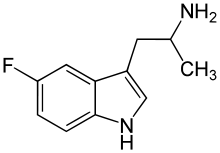

List of substituted α-alkyltryptamines

α-Alkyltryptamines are a group of substituted tryptamines which possess an alkyl group, such as a methyl or ethyl group, attached at the alpha carbon, and in most cases no substitution on the amine nitrogen.[17][18][19] α-Alkylation of tryptamine makes it much more metabolically stable and resistant to degradation by monoamine oxidase, resulting in increased potency and greatly lengthened half-life.[19] This is analogous to α-methylation of phenethylamine into amphetamine.[19]

5-Fluoro-αMT | 1-(5-fluoro-1H-indol-3-yl)propan-2-amine | 712-08-3 |

5-Fluoro-αET | 1-(5-fluoro-1H-indol-3-yl)butan-2-amine | 1380137-98-3 |